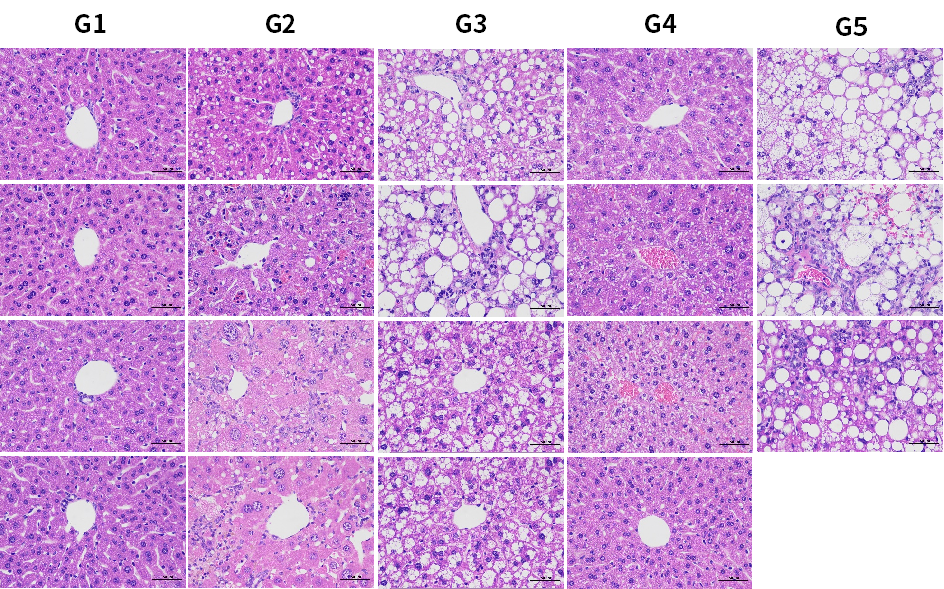

图7. HSD诱导6周后各组小鼠H&E染色代表图。结果显示,HSD饮食诱导下,肝脏特异性过表达hPNPLA3 I148M小鼠出现明显脂肪空泡(G3,G5)。